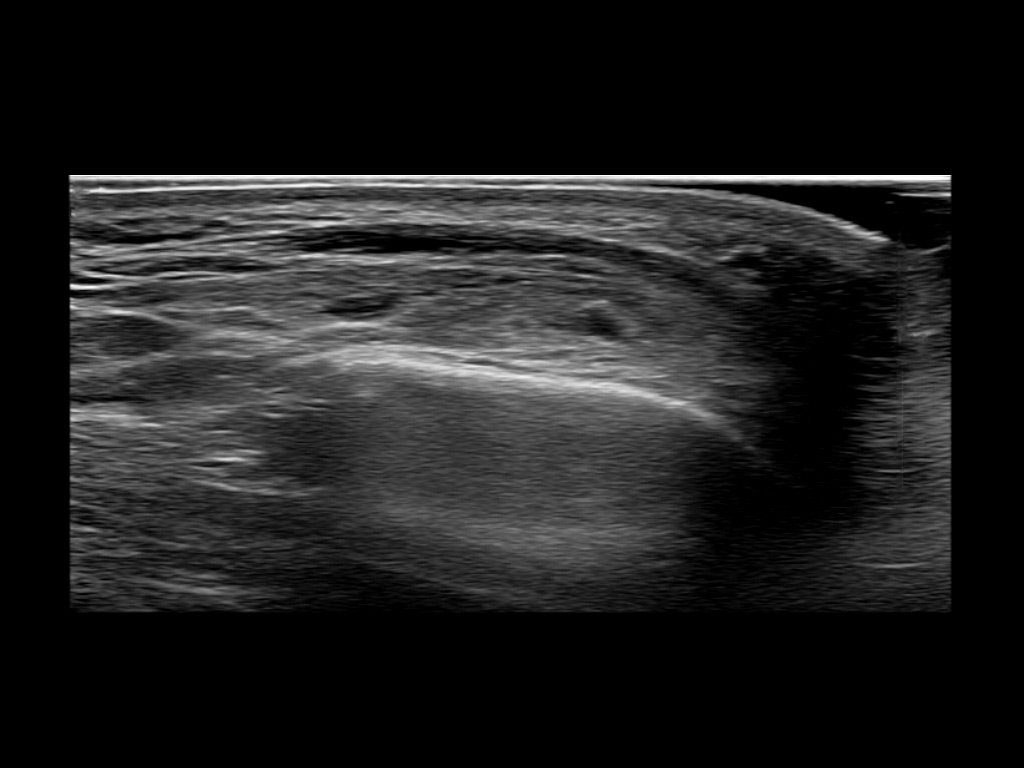

Study the first image to recognize the different layers. If you are sure about the layers, swipe to the second image to view the answer (if applicable).

Hover over an image to view the secondary image or click on the image title for more information.